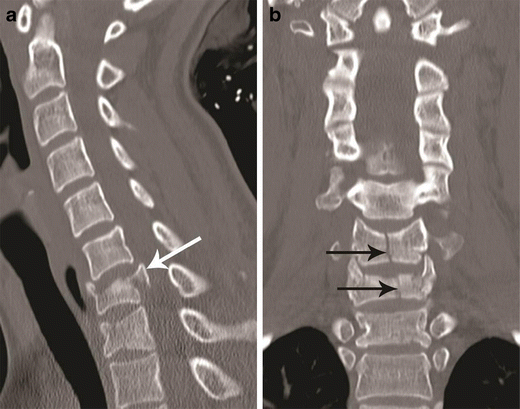

Burst fracture. a Mid-sagittal CT image showing a comminuted fracture of C7 with nearly symmetrical loss of vertebral body height with extension of the fracture to the posterior cortex and retropulsion of fragment from the posterospuerior cortex of C7 (white arrow)—suggestive of a burst fracture. Vertebral body comminution is better seen on axial images as shown in Fig. 9b. b Coronal CT image showing a vertical split fracture of C6 and C7 (black arrows). These fractures are oriented in the sagittal plane, hence best seen on coronal images and highly suggestive of axial loading injury